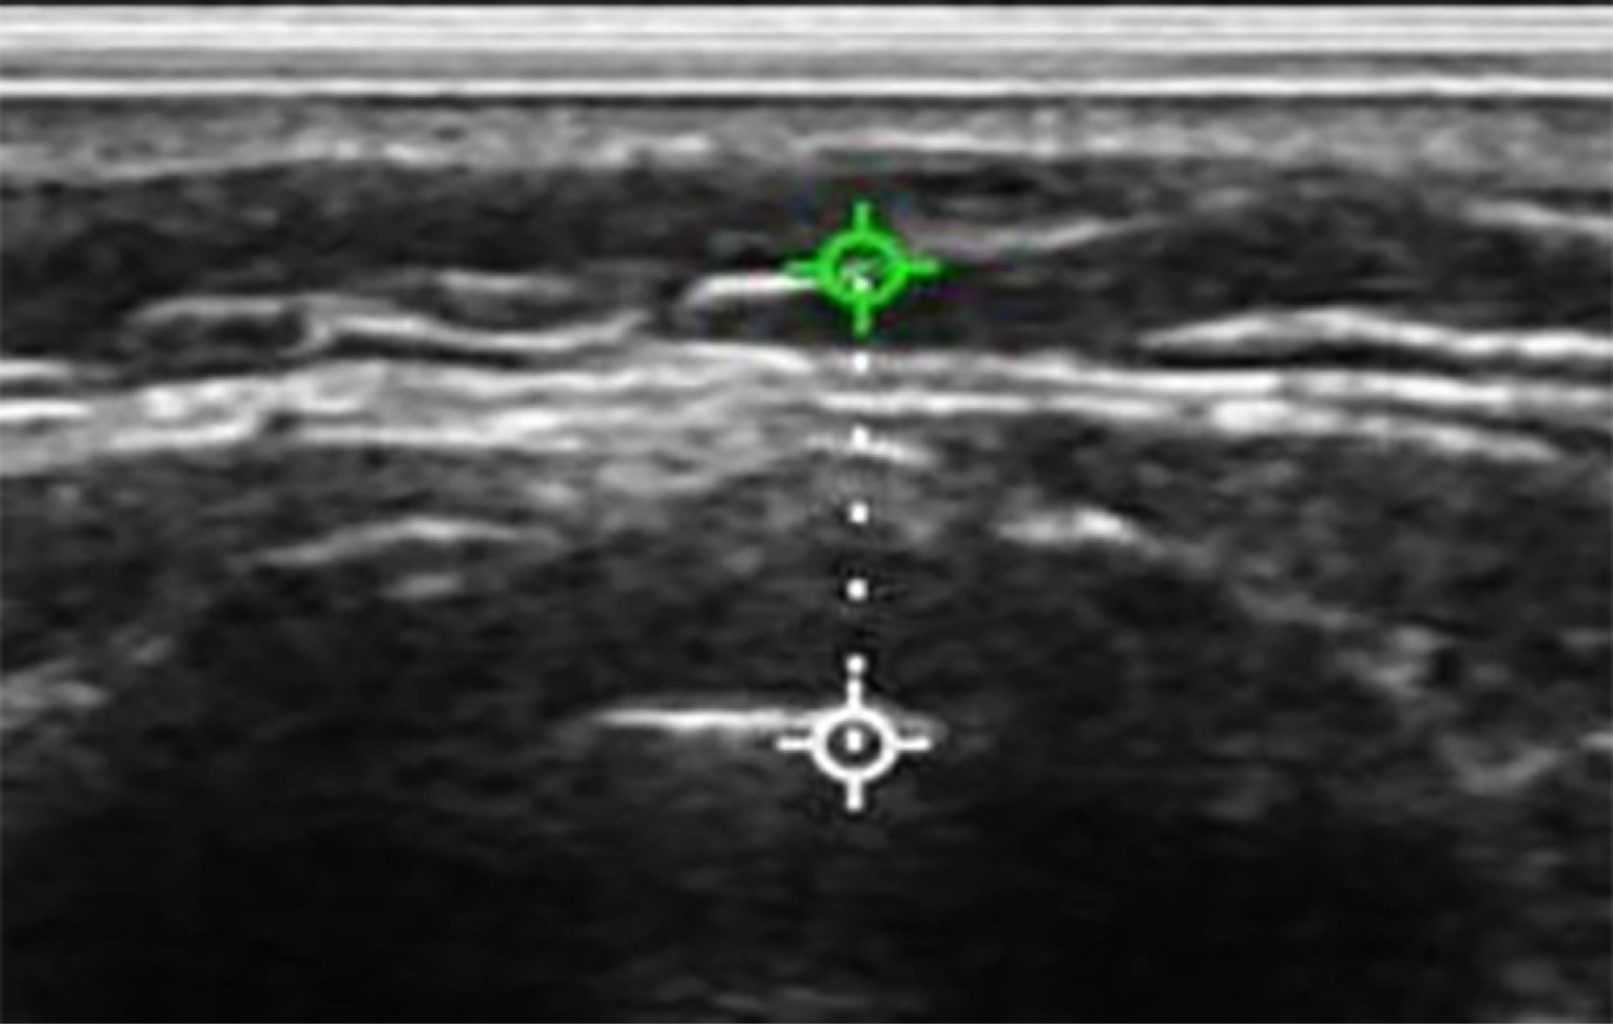

Para la correcta medición de la grasa pretraqueal: se colocó al paciente en estado consciente en posición supina con cabeza en hiperextensión (posición de olfateo), con el objetivo de exponer el cuello para su medición. Se utilizó el ultrasonido de la marca Sonowireless Plus I adaptado a un transductor lineal con frecuencias de 7.5 y 10 MHz. El ultrasonido se conectó de forma inalámbrica a un teléfono celular personal para visualizar imagen y tomar medidas con herramienta de regla incluida en la aplicación "WirelessKUS" (Figuras 1 y 2). El transductor se colocó entre la piel y membrana cricotiroidea. Para visualizar la grasa pretraqueal del paciente se evaluó la distancia comprendida entre la piel y el anillo traqueal.

Figura 1

Figura 2